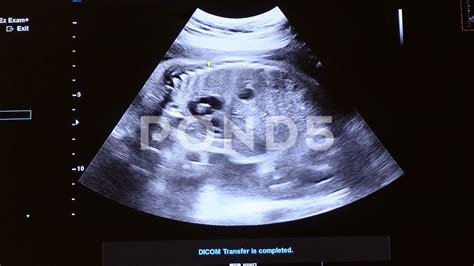

Prenatal care is a crucial aspect of ensuring the health and well-being of both the mother and the developing baby. Among the various prenatal tests and screenings, 28 Weeks Sonography stands out as a pivotal milestone. This ultrasound examination, typically performed around the 28th week of pregnancy, provides valuable insights into the baby's development and the mother's health. Understanding the significance of this procedure can help expectant parents prepare for what to expect and how to interpret the results.

28 Weeks Sonography is a routine ultrasound scan conducted during the third trimester of pregnancy. This scan is often referred to as the "anomaly scan" or "mid-pregnancy scan" and is usually performed between 26 and 28 weeks of gestation. The primary goal of this ultrasound is to assess the baby's growth, development, and overall health. It also helps in identifying any potential complications that may require further monitoring or intervention.

During a 28 Weeks Sonography scan, the expectant mother will lie on an examination table with her abdomen exposed. A gel is applied to the abdomen to enhance the transmission of ultrasound waves. A transducer, a handheld device, is then moved over the abdomen to capture images of the baby. The procedure is painless and non-invasive, typically lasting between 20 to 30 minutes.

These measurements help in estimating the baby's weight and assessing overall growth. The technician will also check for any structural abnormalities in the baby's organs, such as the heart, brain, kidneys, and spine.

After the 28 Weeks Sonography scan, the ultrasound technician will review the images and measurements with the expectant mother. The results are typically discussed with the obstetrician, who will interpret the findings in the context of the mother's overall health and pregnancy history. Key points to consider include:

• Growth Parameters: The measurements of the baby's head, abdomen, and femur are compared to standard growth charts to ensure the baby is developing normally.

• Organ Function: The scan assesses the function and structure of the baby's organs, looking for any signs of abnormalities.

• Amniotic Fluid Levels: Normal levels of amniotic fluid are crucial for the baby's development and movement. Abnormal levels may indicate issues that need further investigation.

• Placental Health: The position and health of the placenta are evaluated to ensure it is functioning properly and providing adequate nutrition to the baby.